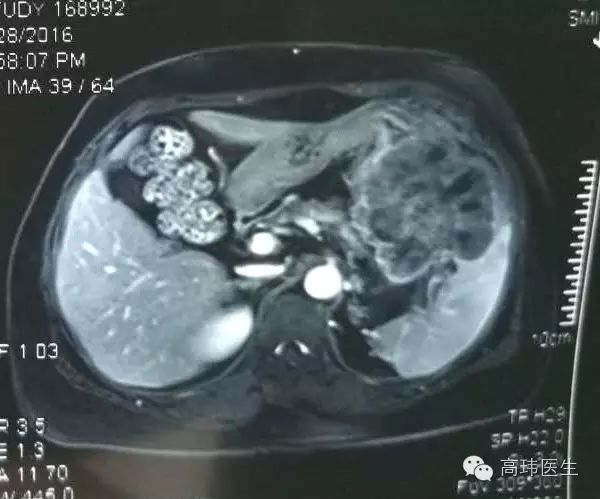

病例60岁女性患者,三年前在山东因结肠脾曲癌行姑息性左半结肠切除术,今3月因腹部不适查肠镜有发现升结肠近肝区、降结肠两处巨大溃疡性肿瘤,全腹增强CT显示结肠癌术后肿瘤复发并侵及邻近胃壁、空肠、胰腺及脾脏,肝右叶考虑转移瘤